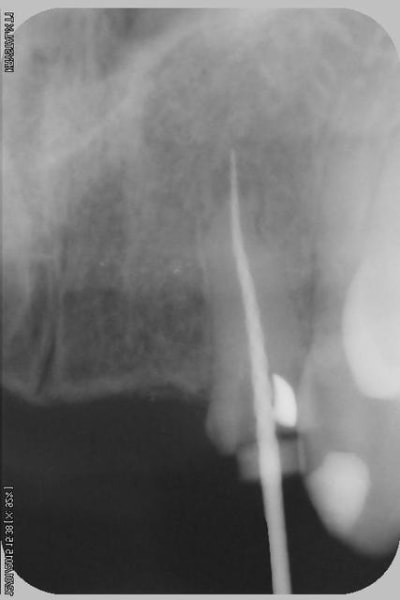

Donc dans un premier temps,je décide d'essayer de retraiter 12/22, de toute façons ça ne peut pas être pire que ce qui tiens depuis 10 ans... enfin 12 mobilité quasiment 3.

ensuite Srew post (bouh...) et résine, afin de pouvoir poser un provisoire et réfléchir à l'avenir du parodonte...car il va y avoir un problème quelle que soit la solution choisie.

Sur la reprise de 22 je pense que tu as fais un beau "tout-droit" à l'apex... le canal devait suivre la courbure.

Tu es bon pour faire une chir-apicale dans quelques mois !

je pense que le tout droit existait déjà..

oup's j'ai omis la digue...

Chir apicale si on garde la dent...

Oui oui, c'est certain ! il y avait au moins une belle butée bien engagée. Ce qui expliquerai que l'ancien traitement n'allait pas jusqu'à l'apex.

Et avec les instruments de rotation continue agressifs de reprise d'endo que l'on a maintenant, on s'engage dans la butée et on la "termine"... ça m'arrive aussi de temps en temps... de toutes façons, repasser de vieilles butées comme ça, même les endos exclusifs n'y arrivent presque jamais et font une chir apicale d'emblée.